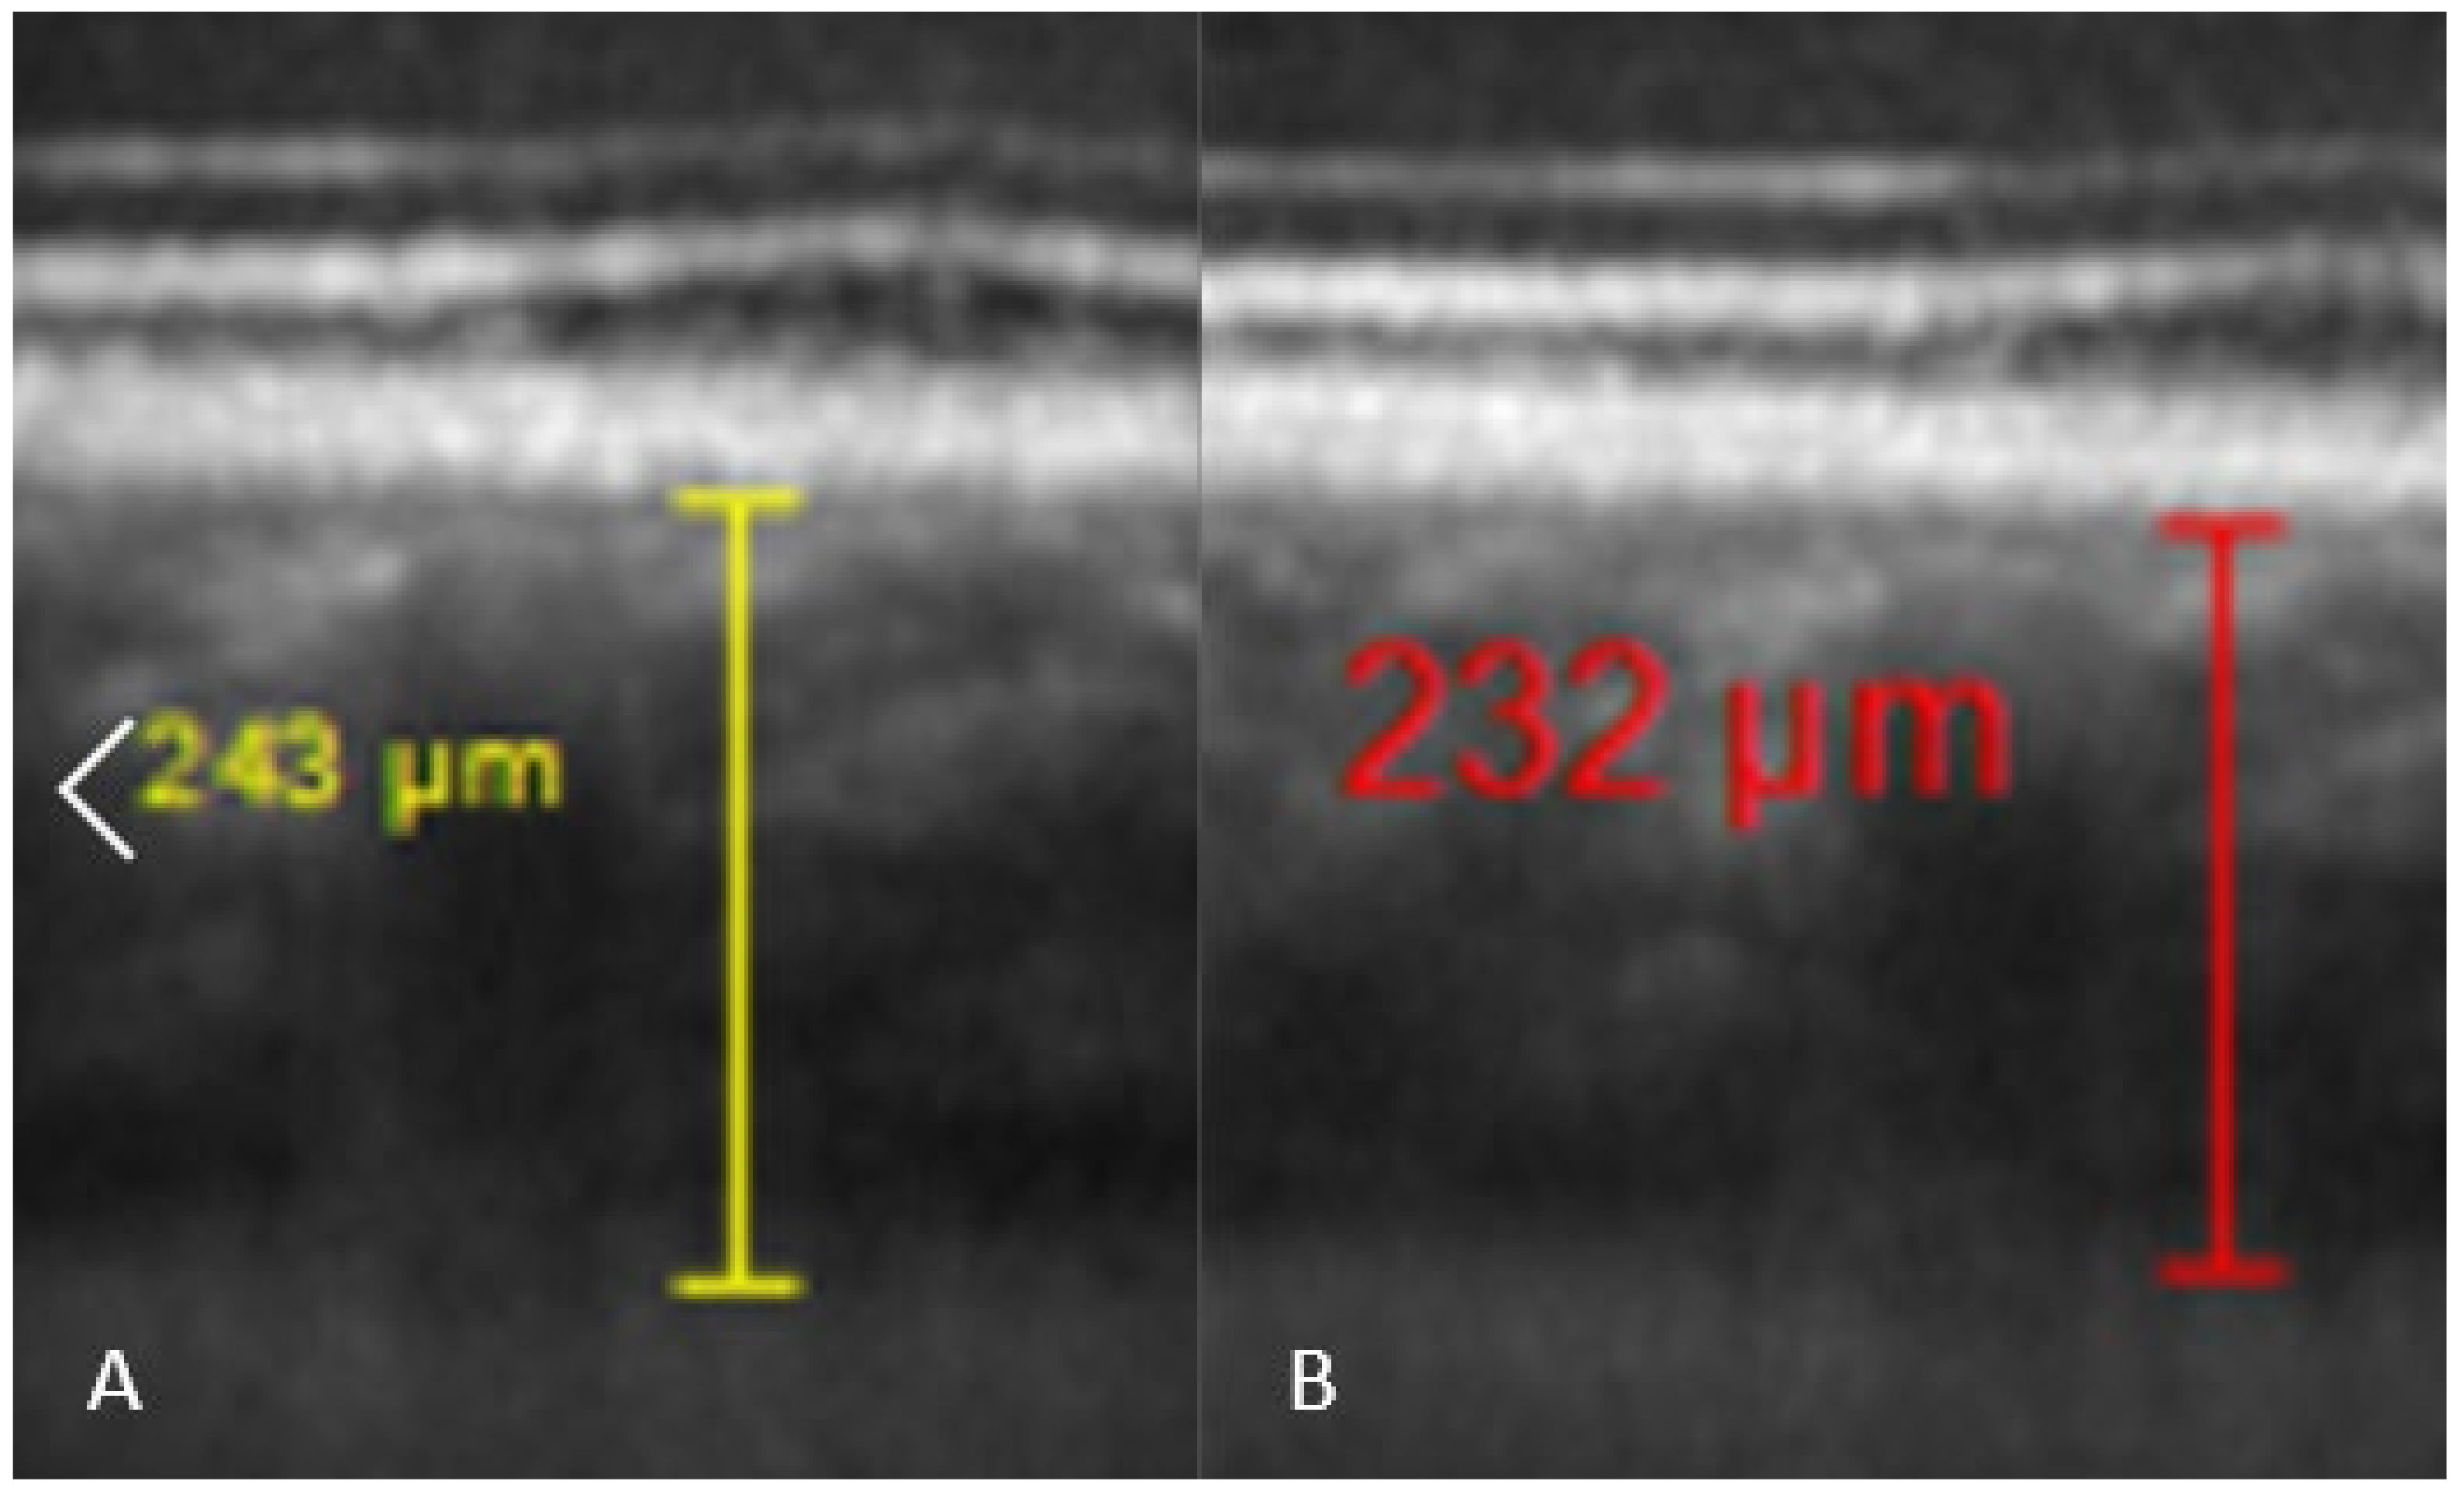

5.1. Subfoveal Choroidal Thickness

| SFCT (µm) | 327.1 (±102.0) | 318.1 (±109.7) | 0.0326 | 322.2 (±102.1) | 0.2434 |